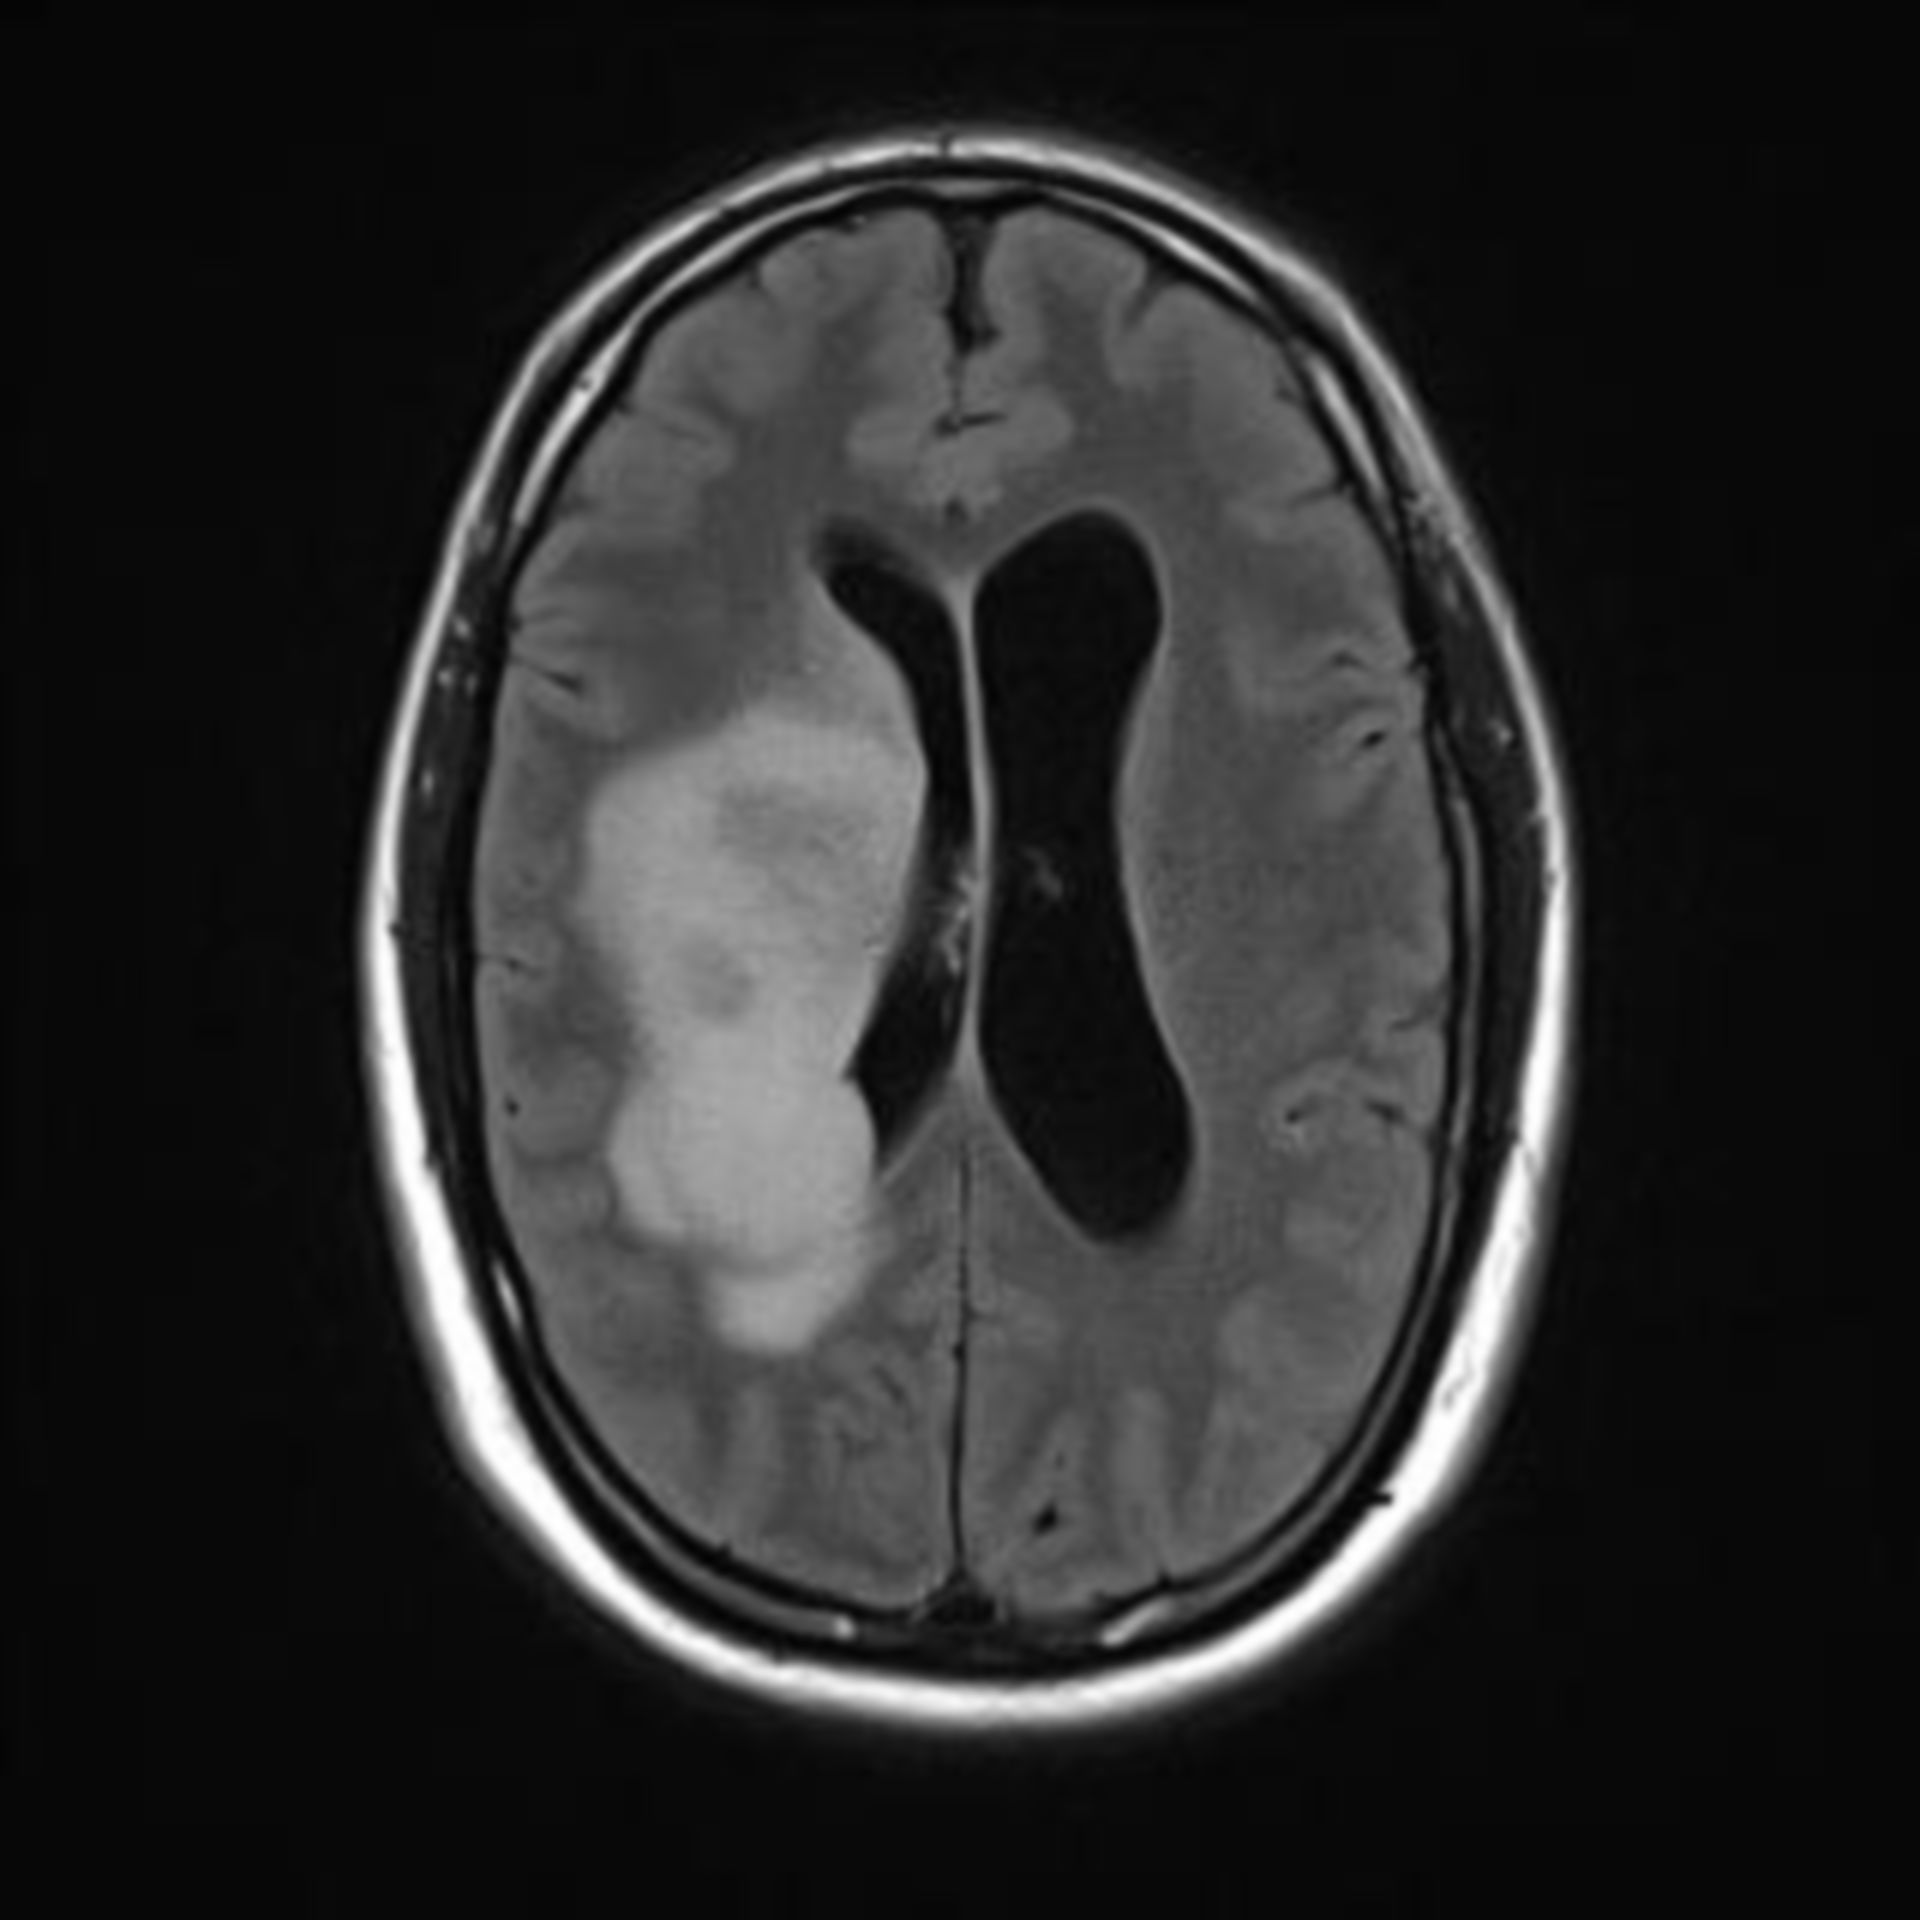

MRT Bild, könnte das ein Tumor sein? Kennt sich jemand damit aus? Könnte die helle Fläche ein … Myokarditis (MRT) – DocCheck

?wer kann helfen?ist in diesen MRT ein Tumor sichtbar? MRT abdomen – DocCheck

MRT Bilder-Hubbel-??? Hilfe (Kopf) รีวิว คอนโด Niche MONO อิสรภาพ เพียง 200 เมตร จาก MRT อิสรภาพ ใกล้ รพ.ศิริราช